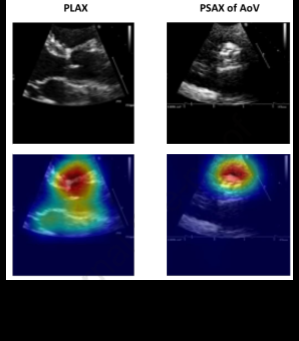

Diving further into view classification, scientific guidelines are decisive in establishing the optimal echocardiographic views to assess pathology. Certain deep-learning studies have revealed, however, that alternative views may be more informative. Take for instance Vukadinovic and colleagues' findings that in a view-informed attention network, image factors that are beyond those known in disease guidelines are considered.51 Morphological factors considered by "black-box" deep-learning models elude researchers and are an active area of investigation, though methods like Grad-CAM visualizations may provide insight into the features models appraise toward their classification.

Grad-CAM heatmaps overlaid on PLAX and PSAX of AoV echocardiographic views, showing model attention regions.

Grad-CAM visualizations. Attention maps overlaid on parasternal long-axis (PLAX) and parasternal short-axis at the aortic valve (PSAX of AoV) views illustrate the morphological regions deep-learning models appraise during classification.